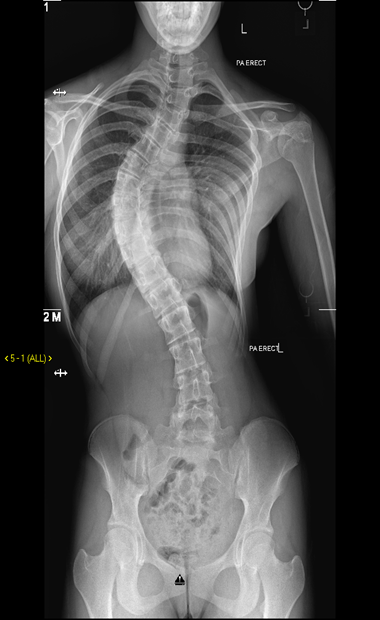

- Scoliosis is a curvature of the spine to the side.

- While the actual twisting and curving of the spine can often be seen, other visible signs of a scoliosis can include uneven shoulders, ribs poking out on one side and an uneven waist.

It can range from close monitoring in our dedicated scoliosis clinics with regular x ray follow-up to surgical correction of the curve.